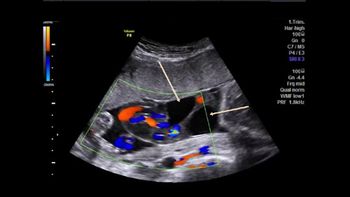

Challenge your diagnostic skills: What's going on with this umbilical cord?

Challenge your diagnostic skills: What's causing this woman's pelvic discomfort?